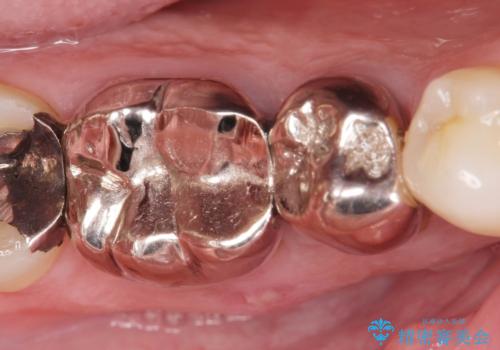

- 食事のたびに、銀歯の間や周囲に食ベカスが挟まったり溜まったりすることの改善を求めて来院されました。

銀歯の形状に問題があり、食べかすの詰まりやすい状況を、精度の高いセラミッククラウンに置き替えることで不快症状の改善を計画します。